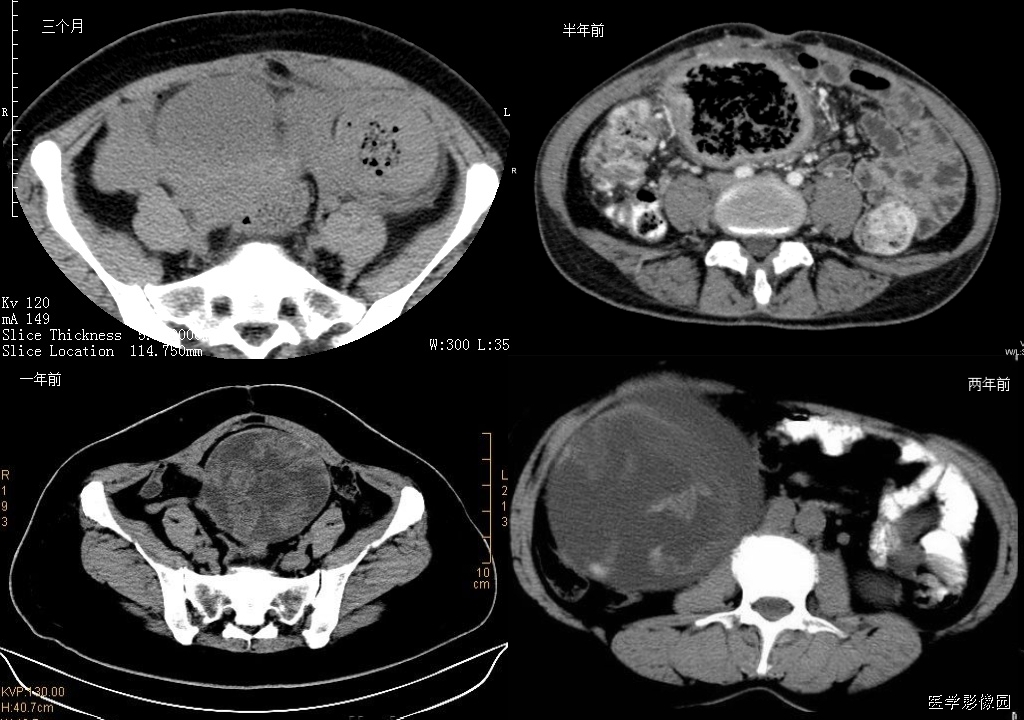

6、蜂窝征

腹腔内残留纱布在人体内引起渗出或液化坏死并纤维包裹形成异物性脓肿(纱布瘤)。纱布瘤的影像特点是:圆形或卵圆形肿块,较大,有完整包膜,薄壁,较少的情况下为后壁,边界较完整,增强后薄膜可以持续强化。不同时期的纱布瘤可以不同的表现:早期(如10各月或半年前)的多表现为蜂窝状;2~5年内一般表现为囊性飘带状;10~20年之后则为实性软组织密度,包膜钙化呈钙化性网状结构。手术过程中残留在人体内的医用纱布所形成的肿瘤样病变。

以下是不同时期纱布瘤的表现: